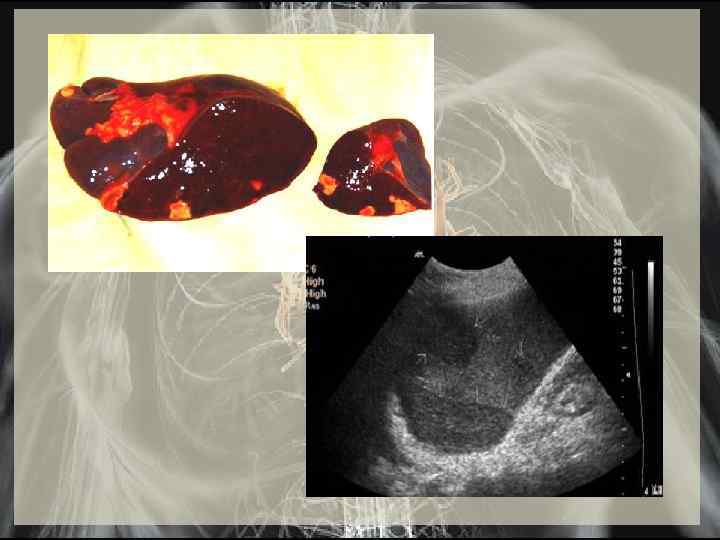

Тромбоэмболические осложнения: • Почки: острые боли, гематурия, протеинурия • Головной мозг гемиплегия, очаговая симптоматика • Селезенка острые боли • Мезентериальные сосуды боли, вплоть до картины «острого живота»

Поражение других органов : • почки (часто) - различные формы гломерулонефрита • увеличение селезенки (часто) • миокардит, при тяжелом течении - быстрое развитие сердечной недостаточности • васкулиты • перикардит (редко) сухой, с небольшим выпотом (гнойный - при наличии абсцессов миокарда и клапанов) • гепатит (редко) - токсического (инфекционного, лекарственного) и/или иммунного генеза • «септические» пневмонии (редко) • артрит(редко)